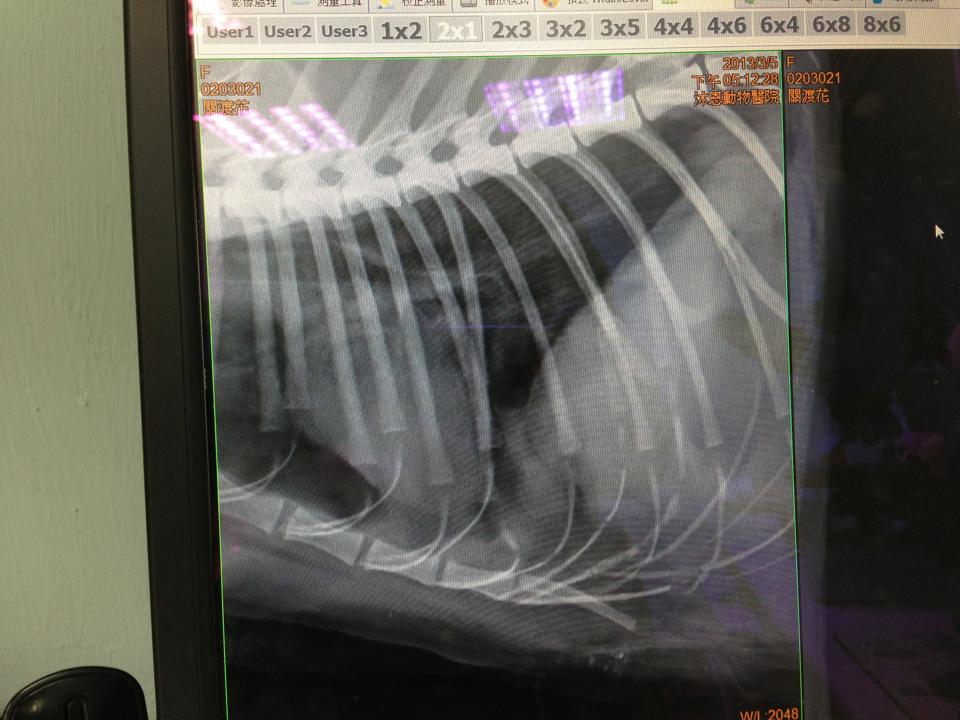

主題: 北投關渡郵局被群狗攻擊的三花貓 申請者姓名: 臺北市支持流浪貓絕育計劃協會 花色: 申請日期: 2013-03-08 11:47:03 申請者部落格: 申請者臉書網址: 所在縣市/合作醫院: 台北市/其他院所醫助專案(醫院請先MAIL溝通) 治療費用: 7025元 需求人數: 8人 已結案 (2013-06-27 14:26:26) 報名人員: 錢曼尼(已付款)、Mai Lin Lai(已付款)、周振禮(已付款)、周振禮、小娃(已付款)、何春生(已付款)、鄭小鄭(已付款)、Js Lee(已付款)、Sunny Chen(已付款)、 候補人員: 動物病情說明: 接到民眾來電,北投關渡郵局有一隻貓咪被狗攻擊躲進車下,因為貓咪會怕人又加上車子的底盤很低無法順利將貓咪救出,協會接到通知第一時間請附近志工小雅過去查看支援,志工Akimasa用網子捕抓送醫,貓咪到院時,體溫只剩下33.6度,肩胛骨斷裂、氣胸,全身多處咬傷,疑似有傷到頸椎神經,隨時有可能會休克,因為血壓很低無法順利上點滴,經過搶救仍在晚間當小天使,醫療費用還請各位幫忙。--謝謝!